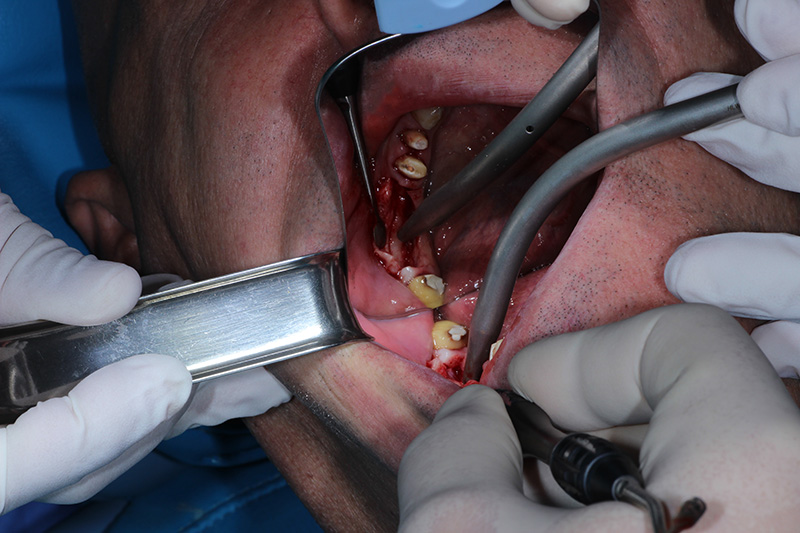

26-ого октября в учебном центре Стом-Лайн был проведен мастер-класс на тему «Закрытый и открытый синус-лифтинг при имплантации, с использованием имплантатов Thommen Medical». Мастер-класс провел главный врач-стоматолог клиники «Нюанс» в Москве Мхитар Казарян.

Мастер-класс начался с представления швейцарских имплантатов Thommen Medical, официальным предтсвителем которых является клиника Стом-Лайн. Далее были проведены обсуждения предстоящей операции и исследования компьютерной томографии, после чего участники смогли присутствовать на операции или следить за ней из учебного центра.

Во время операции доктор Казарян представил на практике особенности и преимущества имплантатов Thommen Medical.